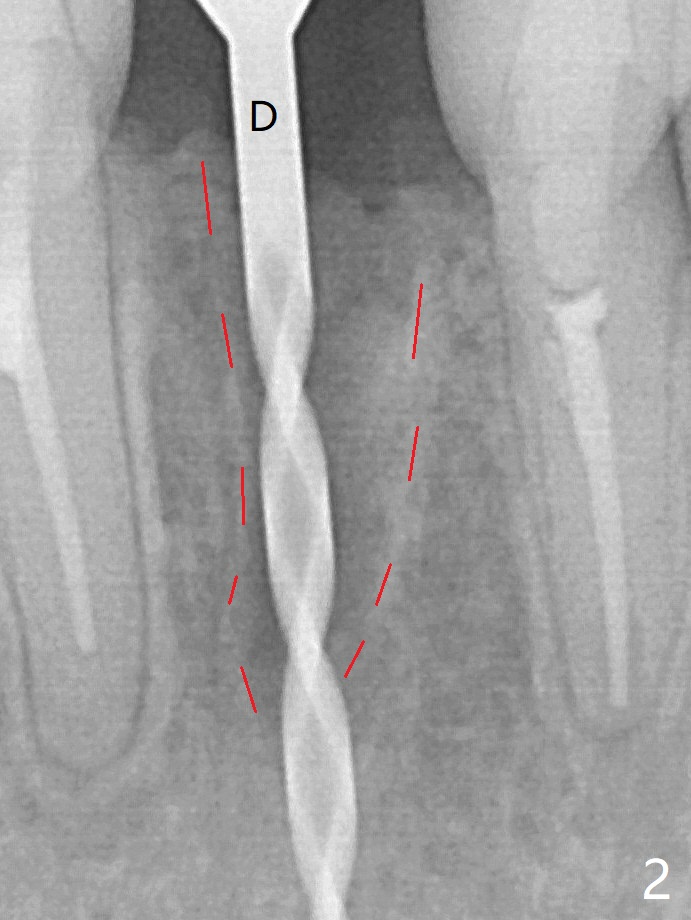

A drawback of implant planning at #25 is not to use a preop PA (Fig.1 (^ fracture line)). The initial trajectory seems to be alright (Fig.2 (red line: socket; D: 1.2 mm drill)), but a 2.5x14(2) mm implant placed is close to the tooth #26 (Fig.3 (allograft having been placed)). The latter may be related to more bone loss in the distal crest 3.5 months postop (Fig.8) and more severe distal papillary recession (Fig.9 *). The meisal bone seems to be wider.